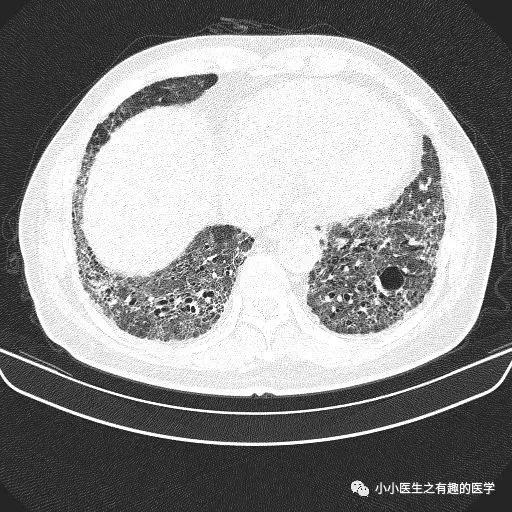

乌漆嘛黑的是肺气肿。

间质性肺炎 合并 肺气肿